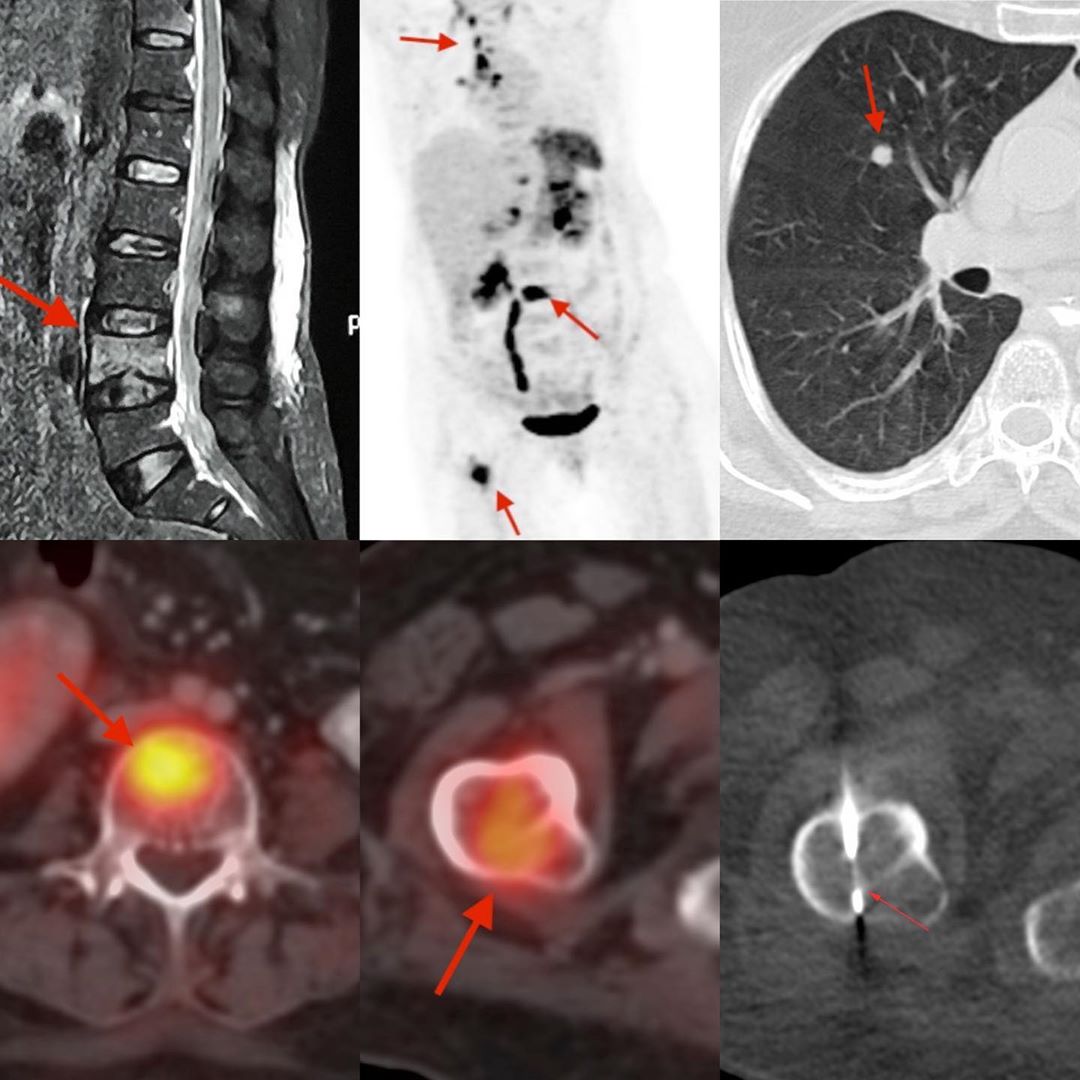

This is a 62-years old lady with fever. After an MRI that showed a focal L4 lesion, a PET/CT was done to look for other lesions in the body given the high chance of metastasis / myeloma / lymphoma.

The PET showed multiple lesions in the bones including the right femoral neck, with mediastinal nodes, lung nodules and a left pleural effusion. There was no primary neoplasm.

The working diagnosis was metastases versus infection.

I felt that the best site to biopsy to get adequate material for all tests would be the right femoral neck. Using an 18G coaxial biopsy gun and lightly tapping through the anterior cortex, I did the biopsy under intravenous sedation. The diagnosis was tuberculosis – it was PCR positive for M. Tuberculosis and not rifampicin resistant.

The case underscores the need to biopsy at all ages and how a PET/CT helps determine the appropriate biopsy site.

Choosing the Appropriate Site for Biopsy – Tuberculosis Femur Neck